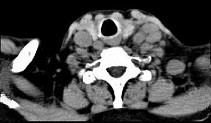

问题 女,69岁,低热、乏力三月余,消瘦,食欲不佳,PE:腹股沟触及多个肿大的淋巴结,质较硬,尚可移动,CT如图所示,最可能诊断为()

选项 A.淋巴瘤 B.颈淋巴结结核 C.颈淋巴结结核 D.结节病 E.淋巴结炎

答案 A